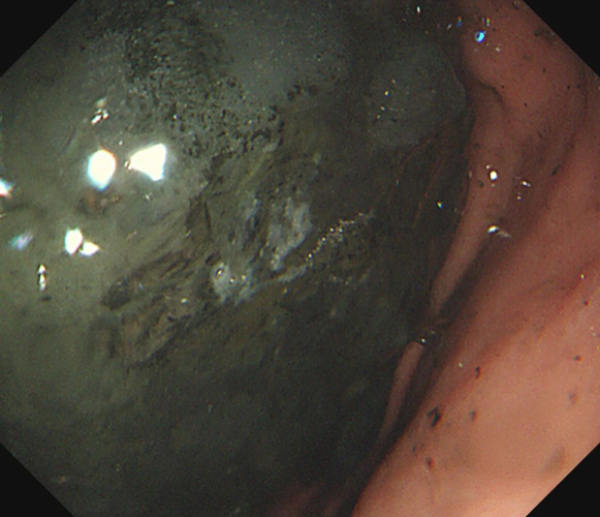

这是一个十分棘手的病例,若采用传统外科改道手术,创伤大、恢复慢;若放置传统十二指肠支架,则需经过肿瘤区域,支架易被压迫或堵塞,通畅时间短,梗阻容易复发。与此同时,患者虽经十余天的禁食禁水与胃肠减压,但其胃内仍潴留着大量纤维性食物残渣与液体,难以进行内镜诊疗。

术前,患者禁食禁水十天后仍然胃潴留严重